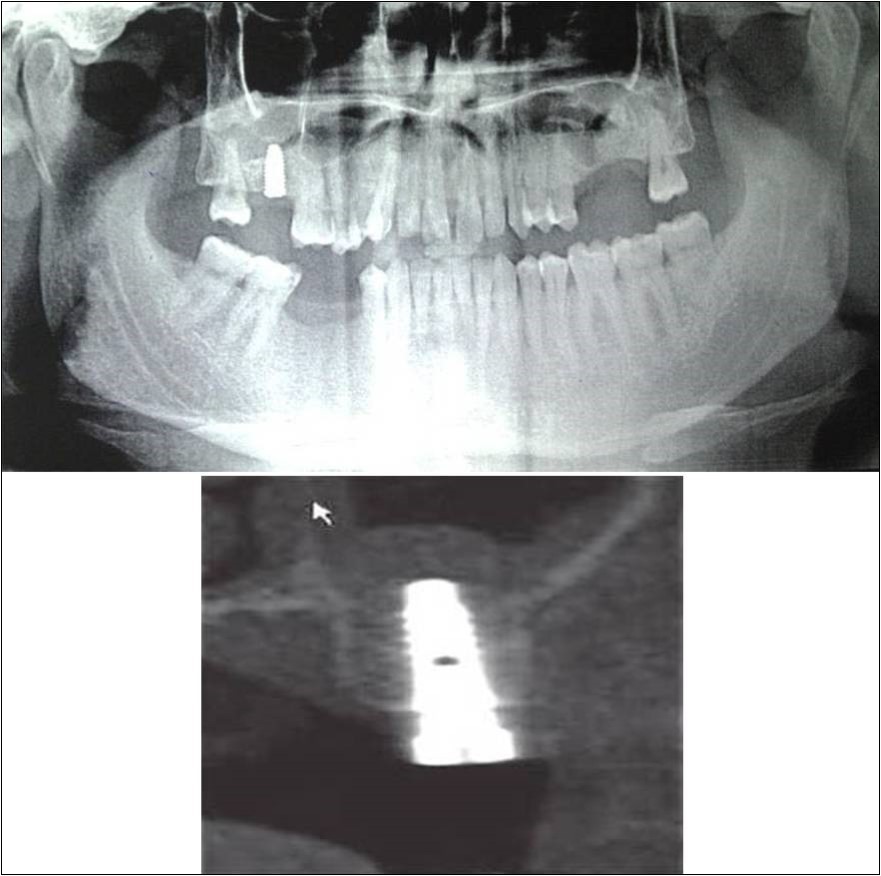

Figure 15.a,b. Pre-treatment OPG and cross section of CBCT showing residual alveolar bone height for Case No.5;

Figure 16.a,b. Post-treatment OPG and cross section of CBCT showing residual alveolar bone height for Case No.5;